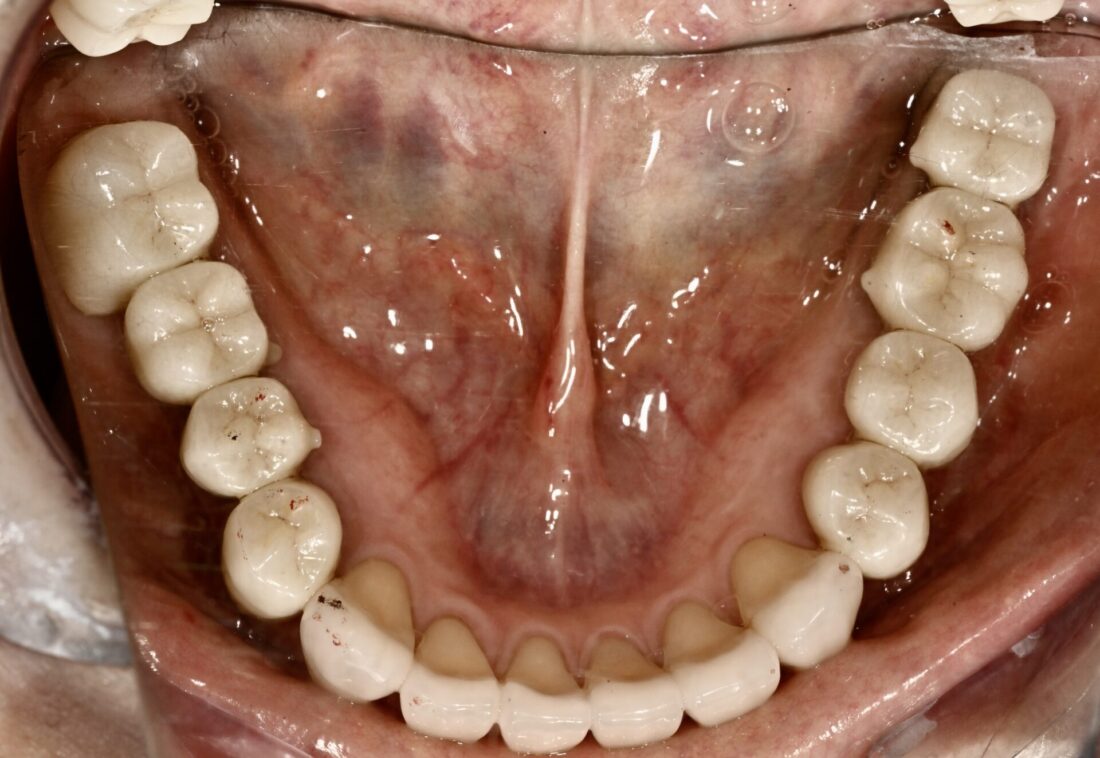

術後(3年・メインテナンス中)

どちらが良いか判断はお任せします。

時間もかかりましたが、患者さんは大変満足されています。